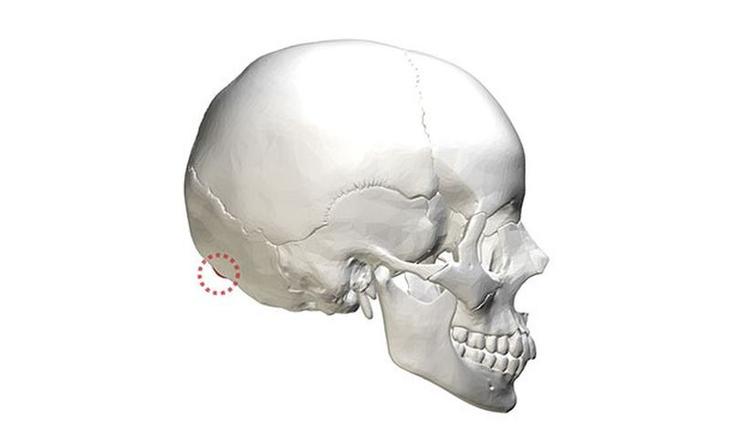

9) Форма черепа тоже разнится. Так, внешний затылочный бугор (расположенный в нижней задней части черепа) несколько больше у мужчин, чем у женщин.